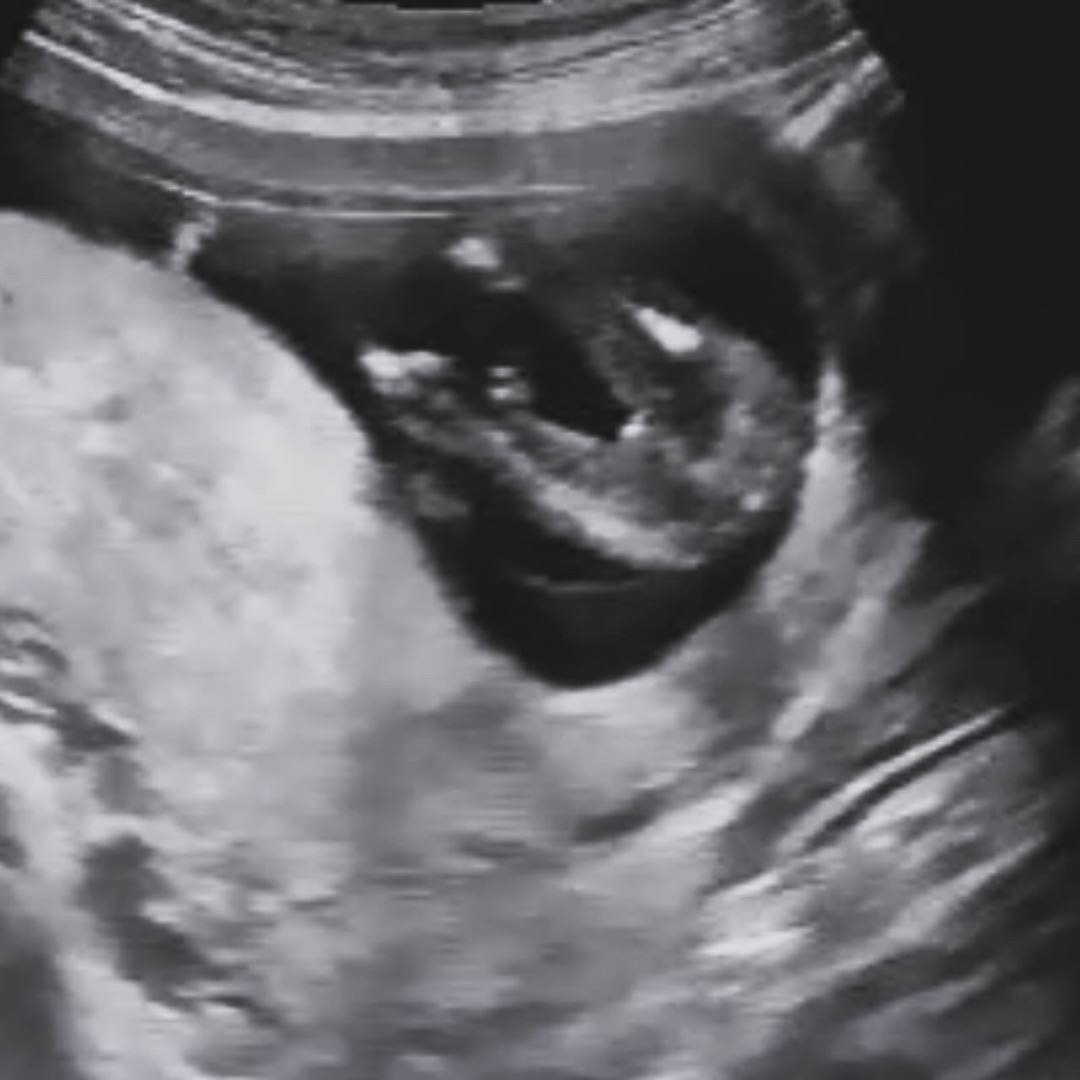

아들 둘에 딸 확정받았어요ㅠㅠ

12주부터 딸 90프로라고 하셨는데 반전없이 딸이네요>.< 앞으로도 반전 없을거래요 ㅎㅎㅎㅎ 딸기운 받아가셔요💛💛💛💛